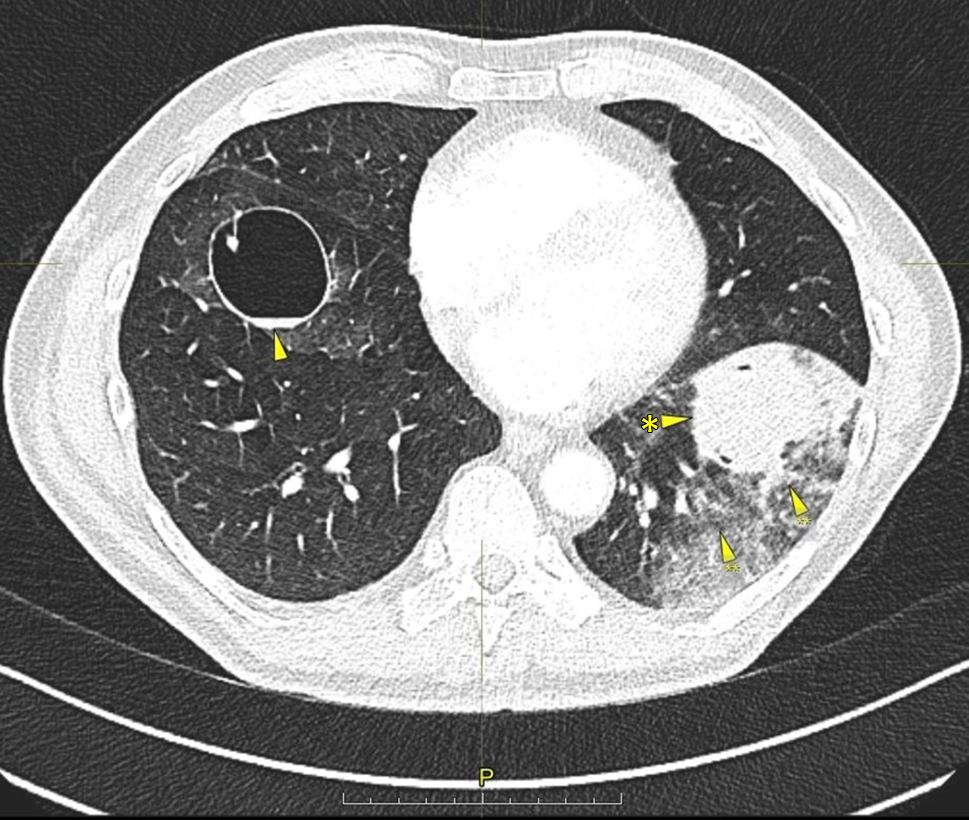

Thoracic CT scan again showed progression. The bilateral lesions had increased in maximum diameter by 3 to 6 mm each, and measured between 10 and 47 mm (Fig. 1). After chest-tube drainage the lung re-expanded; however, there was a pronounced pulmopleural fistula. During thoracoscopy, a ruptured cyst in the apical segment of the lower lobe was identified and removed by wedge resection.

Fig. 1

Thin-walled pulmonary cysts in the right and left lower lobes in the a upper, b middle, and c lower lung fields

Thoracic CT scan revealed another increase in size of the cysts by an average of 5 mm. A large one in the left lower lobe was filled with liquid and surrounded by dense intrapulmonary opacity, suggesting hemorrhage (Fig. 3). By interventional radiology, the segmental pulmonary arteries 8 and 9 on the left side were identified as the source of the bleeding and were coiled, whereupon hemoptysis subsided (Figs. 4 and 5). The chest tube could be removed uneventfully.

Fig. 3

Pulmonary cyst in the right lower lobe (arrow), pulmonary liquid-filled cyst (arrow with asterisk) in the left lower lobe surrounded by dense intrapulmonary opacity (arrows with double asterisks)